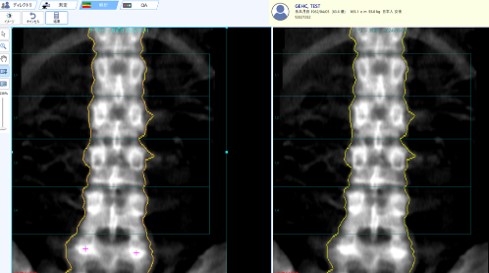

3-2. 2回目以降の解析時のポイント

「ROIを全て自分で設定する」という装置もあるが、GEヘルスケア社のDXA装置では、椎体のROIや大腿骨転子部・頚部のROIが撮影後個々の骨形態に合わせて自動で設定される。一度設定したROIは、次回以降の検査でコピーして使用することもできるため、誰が検査しても同様の解析ができ、再現性の点で有用である。普段X線写真について見慣れないスタッフにとっては特に重宝される。もちろん微妙なズレは適宜修正できるようにもなっている。

Clinical Tips_yokohamashitobu12.jpg

コピーROI機能

一度設定したROIは、次回以降の検査でコピーして使用することができる。